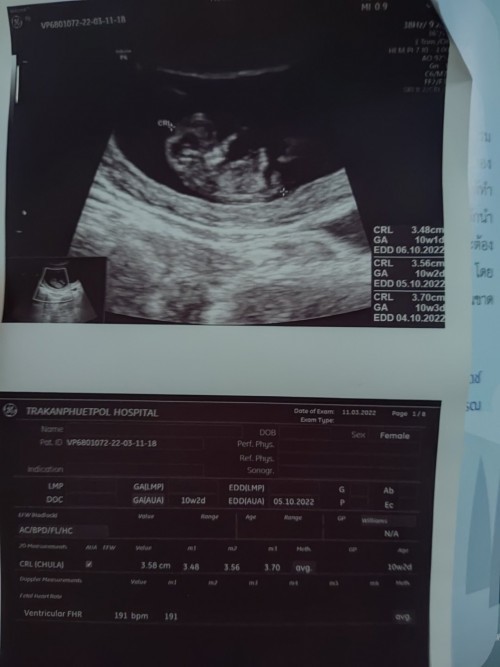

10วีคค่ะ

Post reply image